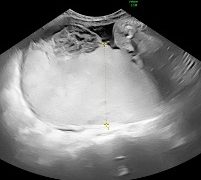

Casi del Mese di Dicembre 2024

Cari soci, finalmente on line le soluzioni dei casi del mese di Dicembre. Grazie a Sara Zullino e Mara Albanese!! Caso 1 - video [pdf-embedder url="https://www.sieog.it/wp-content/uploads/2024/12/Casodelmese_Dicembre2024caso-risposte_gineco.pdf"...